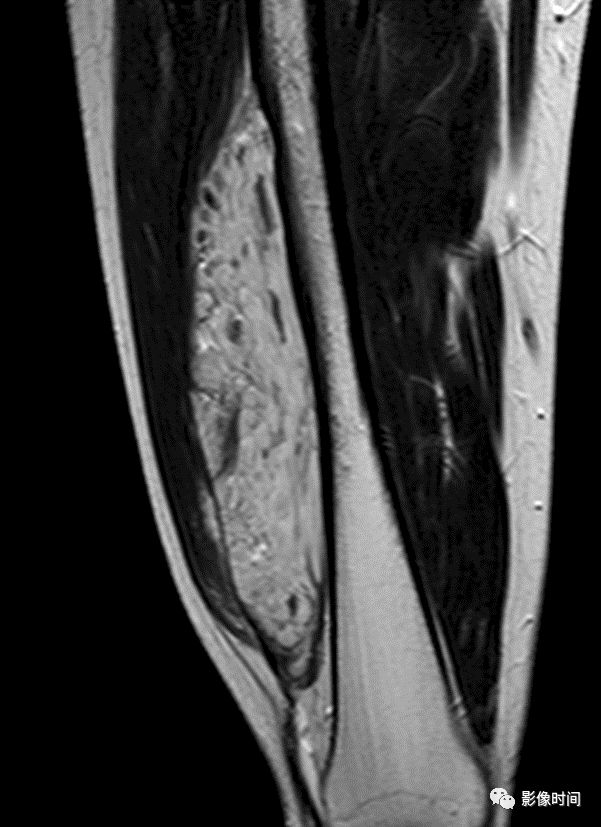

由于瘤软骨多由富含水分及粘多糖的透明软骨构成,故 T1WI 呈偏低信号,T2WI 或 PDWI 呈明显高信号,被低信号的纤维间隔分开呈分叶状(图 24、图 25a-b),增强扫描多呈不均匀分隔状强化(图 25c),主要是纤维间隔强化,瘤软骨强化不明显之故。

图 24  瘤软骨:内生软骨瘤

图 25  瘤软骨:内生软骨瘤